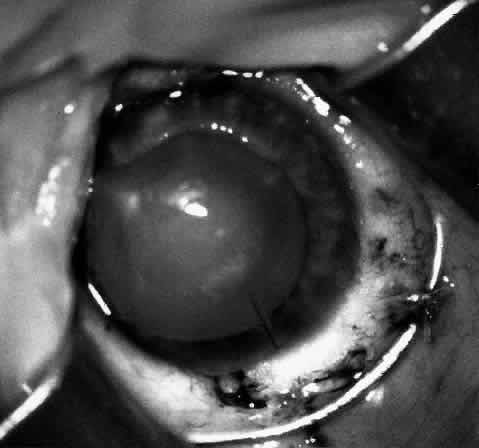

Children who have traumatic cataracts with corneal lacerations are well served by this procedure because the injury often destroys the capsular support that can be used to stabilize an intraocular lens.16–18 The epikeratophakia graft provides structural support for the weakened cornea and minimizes the induced irregular and regular astigmatism, in addition to correcting the optical error (Figs. 3 AND 4).

Fig. 3. Lacerated cornea with a hyphema. (Morgan KS, Ellis GS, Marvelli TL, Arffa RC: Epikeratophakia in children with traumatic cataracts. J Pediatr Ophthalmol Strabismus 23: 108–113, 1986)